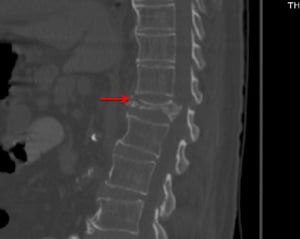

Questa scansione TC (proiezione sagittale) mostra una marcata frattura da compressione di T12 con una malattia degenerativa lieve (p. es., osteofiti del corpo vertebrale anteriore) in altra sede.

© Springer Science+Business Media